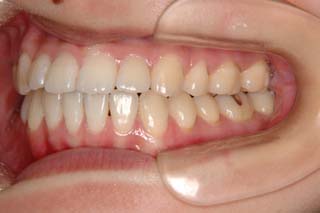

外科症例(アゴの輪郭でお悩みの方) 下顎前突

装置撤去です。動的処置は2年弱でしたので、通常のマルチブラケット治療とそれほど治療期間は変わりません。しかしながら、わずかな正中のズレが残ってしまいました。大きくは改善したのですが、左右のズレというものは、比較的、後戻りが現れやすい問題です。筋肉の影響によるものや、咬合平面の傾斜が左右的に水平でない事などが関係しているような気がします。今後は保定治療に移行し、数年にわたって咬合の安定状態を管理していきます。